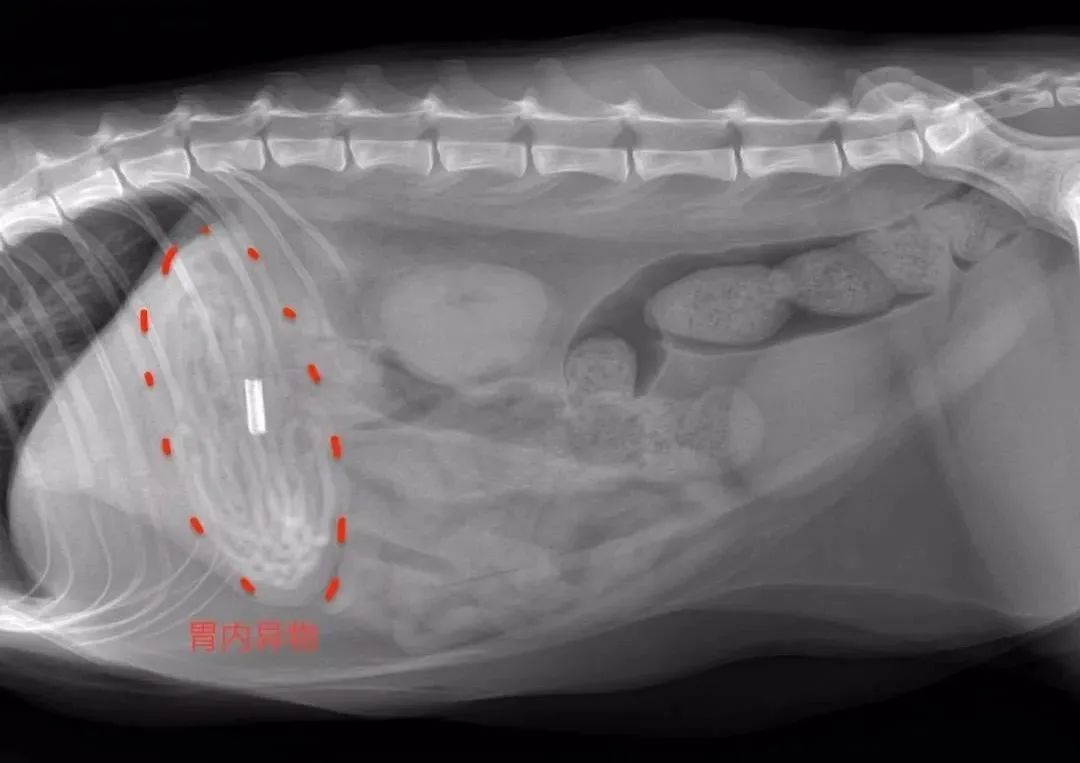

但异食终究是异食,异食容易让猫咪误食异物,而导致腹泻,或是中毒、胃肠梗阻等等危险。

▲猫咪误食主人的发圈(需手术取出)